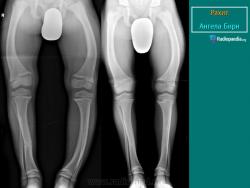

Лишение скелета определенной части неорганических веществ содействует увеличению пластичности костей. Последнее достигает при рахите такой степени, что под влиянием мышечной тяги и нагрузки наступает деформация скелета, которая сказывается прежде всего на изменении формы длинных трубчатых костей. Искривления длинных трубчатых костей на уровне диафизов и деформация суставов проявляются особенно резко на нижних конечностях, где фактор нагрузки наиболее выражен. Деформации эти весьма многообразны и при резко выраженной степени наряду с косметическими нарушениями вызывают функциональные расстройства. В норме линия, соединяющая головку бедра с основанием Ш плюсневой кости, проходит через середину коленной чашки. Угол, образованный между осью голени и бедра, равен в норме у мужчин 173°, а у женщин 172°. Уменьшение или увеличение этого угла за счет боковых отклонений во фронтальной плоскости приводит к образованию genua vara или genua valga. При варусном искривлении коленного сустава вершина образованного угла обращена в наружную сторону, при вальгусной деформации - кнутри.